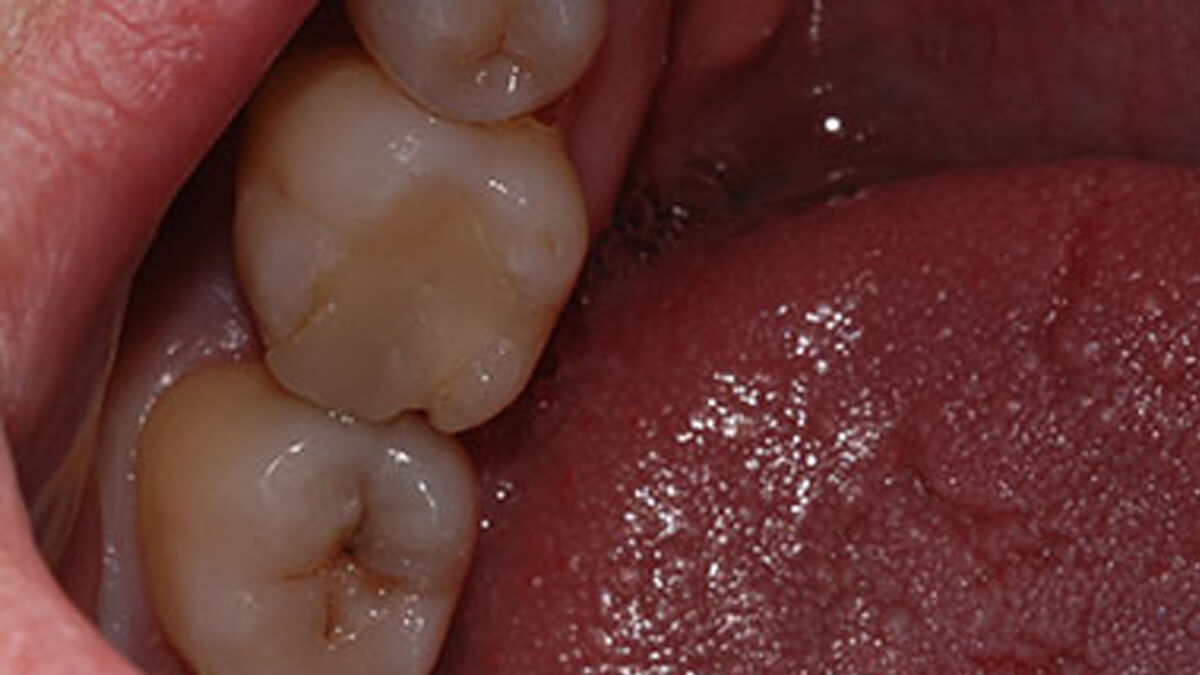

Általában ha a fognak csak egy kisebb része szuvas, a hiányzó rész kitisztítás után tömőanyaggal pótolható. A töméskészítést helyi érzéstelenítésben végezzük, egy alkalmat vesz igénybe. A tömőanyag egy speciális műanyag, kompozit, amely mind színében, mind fizikai tulajdonságaiban nagymértékben hasonlít a természetes foghoz, ezért alkalmas tartós és esztétikus tömések készítésére. Töméskészítés során a gyurmaszerű anyagot kis adagokban helyezzük az üregbe, majd az egyes rétegeket speciális lámpával világítjuk meg, melynek hatására megszilárdulnak. A tömés elkészültével az anyag kötése befejeződik, a fog terhelhető.

A tömőanyag tulajdonságaiból adódóan ma már, ha az üreg nem túl nagy, minden fogcsoport tömésére alkalmazható. Rágófogakban képes helyreállítani a funkciót, azaz egy erős, a rágóerőkkel szemben ellenálló tömés készíthető, frontfogakba (metszőfogak) pedig készülhet olyan esztétikus, észrevehetetlen tömés, mely kedvezően befolyásolhatja megjelenésünket, arckarakterünket.